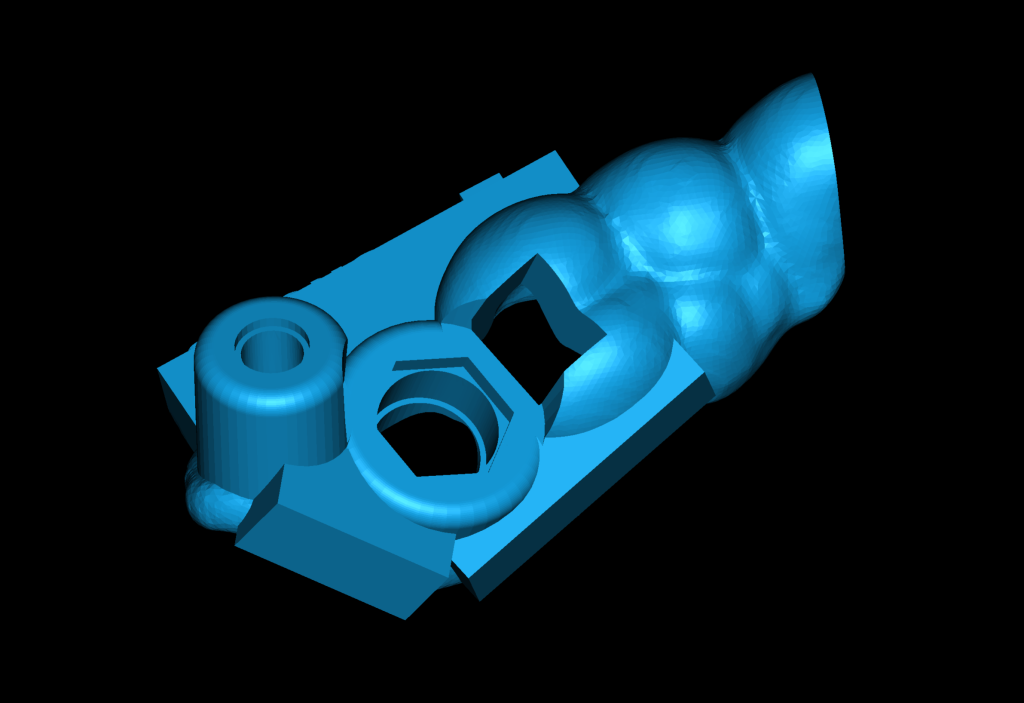

3D reconstruction created on the basis of DICOM and an intraoral scan in the Diagnocat STL module allows you to choose the optimal size and location of the implants

Based on digital models, a virtual design of a template has been planned for the replacement of tooth 36 (Universal 19)